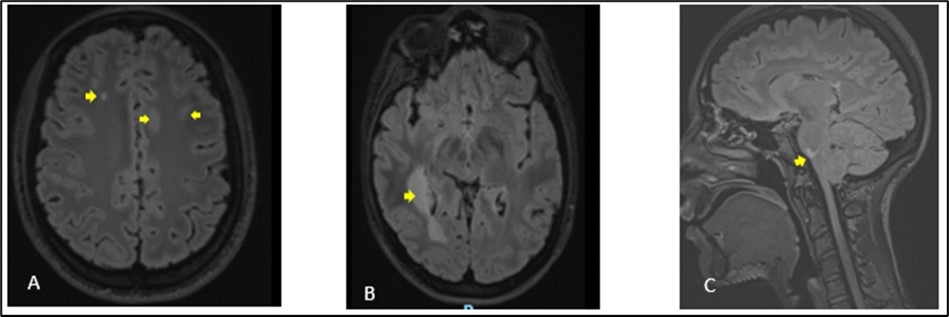

A 27-year-old girl presented at the emergency department, at a hospital in the Paris region on March 9, 2020 with complaints of left interscapular pain, paresthesias and weakness in the ipsilateral upper limb. These symptoms followed paresthesias on the fingertips of her right hand the day before her admission. She did not report fever, sphincter disorder or gait disturbance. No eye symptoms reported. In her medical history, she was treated two weeks earlier for pneumonia with COVID-19. There was no another previous infectious episode apart from the COVID-19. She had no history of diabetes, hypertension, cerebrovascular disease or migraine. She had not history of multiple sclerosis or Neuromyelitis Optica Spectrum Disorder (NMOSD). There was no history of smoking, contraception drugs intake or any prolonged drug intake. On the first examination in the neurology department where she was transferred on the same day of her admission, she had good general condition and was apyretic. She had a pulse rate of 74/min and the blood pressure was at 130/80 mmHg. The neurological evaluation showed on the left side, a muscular weakness grade 4 in the proximal part and grade 3 in the distal part of upper limb, and in the lower limb, the weakness graded at 3 in the distal part, using the Medical Research Council Scale (MRC) for muscle strength. There was no weakness on the right side. Deep tendon reflexes in both left and right were normal. Babinski sign was found on the left side. She presented tactil and algic hypoesthesia in the lower left limb ascending until the C4 level in the left side. There was no perineal sensitive trouble. The remain neurological exam including, higher functions, cranial nerves, was with no particularity. Otherwise, cardiovascular and respiratory systems examination were within normal limits. Blood laboratory tests were within the normal ranges, including complete blood count (CBC), C-Reactive protein, renal and liver functions and blood serum ionogram. Human Immunodeficiency Virus (HIV) tests including p24 antigen and antibodies to HIV were negative. Syphilis serology and Aquaporin 4 antibody were also negative. Encephalic Magnetic Resonance Imaging (MRI) demonstrated scattered hyperintense lesions on FLAIR imaging in deep hemispheric and juxtacortical white matter in supratentorial and in infratentorial floors (Figure 1). Medullary MRI showed T2 hyperintense lesions in left cervical hemi-marrow extending from C3 to C6, at T3, T4, T11 and T12 levels (Figure 2). These lesions were not enhanced after injection of gadolinium. The Cerebrospinal fluid (CSF) appeared to be colorless and clear with no cell detected microscopically; cerebrospinal protein level, 0.4 mg/L, glucose (Glu) level, 3.2 mmol/L; and instant blood glucose level, 5.2 mmol/L. CSF bacterial culture demonstrated no growth after 3 days, and herpes simplex virus 1 and 2, varicella-zoster virus test was negative. Reverse transcription-polymerase chain reaction (RT-PCR) assay test for COVID-19 was negative in the CSF. The final diagnosis was an ADEM secondary to novel coronavirus (nCov) infection. She was given methylprednisolone (1000 mg IV per day for 5 days) followed by Intravenous Immunoglobulin (IVIG) therapy at 0.4 g/kg daily for 5 days. Together with chemotherapy, she received physiotherapy coupled with occupational therapy. The outcome was good with improvement of weakness and paresthesias. There was residual tingling on the fingertips of the left hand. The patient was discharge on day 13.

Figure 1.Cerebral MRI in FLAIR sequences showing multiple hyperintense lesions at the supratentorial (A, B) and infratentorial (C) levels. The largest supratentorial lesion (B) is opposite the right paraventricular white matter, at the level of the posterior horn and measures 55 x 17 mm axially. Presence of a lesion of pons (C) of 6.5 mm.

We have described a case of ADEM post COVID-19 infection in a 27-year-old girl who was taken care of in a hospital in the Paris region. She was treated in the same hospital 2 weeks earlier for an acute respiratory distress syndrome caused by COVID-19 infection. The period of the study was at the beginning of the outbreak of COVID-19 infection in France. COVID-19 is a new entity caused by the severe acute respiratory syndrome coronavirus 2 (SARS CoV-2). It is known to cause respiratory complications, from mild upper respiratory symptoms to acute respiratory failure. ADEM is an immune-mediated inflammatory disorder of the CNS characterized by a widespread demyelination that predominantly involves the white matter of the brain and spinal cord. The condition is usually precipitated by a viral infection or vaccination 7. For this, it is also named post-infectious encephalomyelitis. The infection typically comes before the onset of symptoms of approximately 2 days to 4 weeks 8. This was the case of our patient who presented two weeks before the onset of neurological symptoms, a pulmonary infectious episode for which the etiological research revealed a COVID-19 infection. The pathological abnormalities during ADEM are post-infectious changes of immune origin affecting the central nervous system. These changes are present in the small blood vessels of both white and grey matters. As the lesions become older, the macrophages increase and lymphocytes decrease in number. At a late stage of disease foci of fibrillary fibrosis can also be seen in adjacent brain tissue. Although postinfectious encephalomyelitis typically involves the white matter, lesions in grey matter have also been seen and may involve basal ganglia and the thalamus 3, 4. Due to the impossibility to perform an anatomopathological examination in our patient, MRI of the CNS constitute a reliable tool to translate the diffuse CNS damages of the brain as well as of the marrow. These elements are well presented on the imaging performed by our patient (Figures 1, 2). There is a lack of detection in CSF in most cases besides evident inflammation. This raises the possibility that the majority of ADEMs associated with COVID-19 could be the result of immune-mediated mechanisms or molecular mimicry which generates an aberrant neuro-inflammatory loop, so the virus does not need to cross the blood-brain barrier to cause damage to the CNS 9. As with ADEM occurring after other viral infections, the mechanism would be the same in the case of COVID-19 infection. The presence or history of any other systemic infection, particularly viral, would have made the diagnosis unlikely. As the patient had no other infection apart from COVID-19 in the days preceding the neurological symptoms, it is therefore perfectly legitimate to consider this infectious episode as the trigger for the cascade of immune reactions at the origin of the neurological symptoms. In most cases, ADEM has a monophasic course and is self-limiting, with return to neurological baseline within 3 months after the onset of symptoms. Occasionally, a subset of ADEM patients with relapsing disorders, including recurrent disseminated encephalomyelitis (RDEM), multiphasic disseminated encephalomyelitis (MDEM), neuromyelitis optica spectrum disorders (NMOSD), and multiple sclerosis have been reported 10. The clinical presentation is heterogeneous. Typically, patients show prodromal symptoms such as fever, headache, malaise, nausea, and vomiting. The acute phase occurs with encephalopathy, characterized by altered behavior including irritability, confusion and consciousness like lethargy, stupor, or coma associated with multifocal or focal neurological deficits depending on the area involved in the demyelinating process 11. Other neurological findings have been reported in ADEM related to COVID 19. Laura Zelada-Ríos reported in 2021 pyramidal signs (44.4%), brainstem signs (11.1%), cerebellar signs (22.2%), seizures (33.3%) and peripheral nerve compromise (11.1%) 12. ADEM in COVID 19 pediatric patients have been also reported in children 6, 13. MRI plays a key role in the diagnosis of ADEM and should be performed as soon as it is suspected. The typical findings are identified as lesions with signal hyper-intensity in FLAIR and T2 sequences, they are usually multiple, asymmetric, irregular, poorly defined, and greater than 2 cm. In general, the white matter is affected, although it may involve the deep gray matter, the brainstem, the cerebellum, and the spinal cord 12. MRI is also used to consider differential diagnoses 14 multiple sclerosis (MS), neuromyelitis optica (NMO), and neuromyelitis optica spectrum disorder (NMOSD), which can overlap with ADEM in presentation 15. Among these previous diagnoses, multiple sclerosis remains the most important differential diagnosis of ADEM. Both clinically and paraclinically, these 2 pathologies share almost the same criteria. Thus, Swharz et al, in a cohort of 40 patients, fail to identify any exclusive feature characteristic of either condition. Similarly, cerebrospinal fluid findings are not distinctive enough to allow differentiation between ADEM and multiple sclerosis in a single patient. Even MRI studies were not able to differentiate ADEM from multiple sclerosis. Approximately, 50% of the patients with ADEM had MRI features that were suggestive of multiple sclerosis. however, fever, loss of consciousness, and meningism are infrequently observed but are highly suggestive of ADEM because these symptoms are rare in multiple sclerosis 16. It results from this study of Swharz, that the chronology of the neurological symptoms with a pre-existing systemic infection, viral especially constitutes a very determining profile. These data of the interrogation were at the base of the diagnosis of ADEM post covid of our patient more especially since there were no clinical or paraclinical arguments in favor of another potential differential diagnosis, that is Devic's neuromyelitis optica. Differences exist between encephalitis associated with COVID-19 and ADEM associated with COVID-19, one of them is temporality. Unlike ADEM, neurological symptoms usually appear simultaneously with respiratory symptoms in COVID-19-associated encephalitis. Brain inflammation expressed by pleocytosis is more frequent in encephalitis associated with COVID-19 17. Sharing the same pathophysiological mechanisms as other post-infectious encephalomyelitis, the principles of the treatment of post-COVID ADEM therefore remain similar. The treatment of ADEM is targeted to suppress a presumed aberrant immune response to an infectious agent or a vaccination. Treatment with intravenous corticosteroids (methylprednisolone) or adrenocorticotrophic hormone in large doses has been shown to improve the outcome 18, 19. Corticosteroids are usually associated with plasmapheresis and intravenous immunoglobulin. This association have been shown to produce dramatic improvement in some cases where corticosteroids have failed 16. In some cases, cytotoxic agents have been used with success 18. Functional rehabilitation as a support treatment is a useful contribution even if the publications do not usually mention it. Regarding clinical outcomes, it is generally favorable in the cases of ADEM. This was the case of our patient as well as the results reported by L. Zelada-Ríos et al. 12.